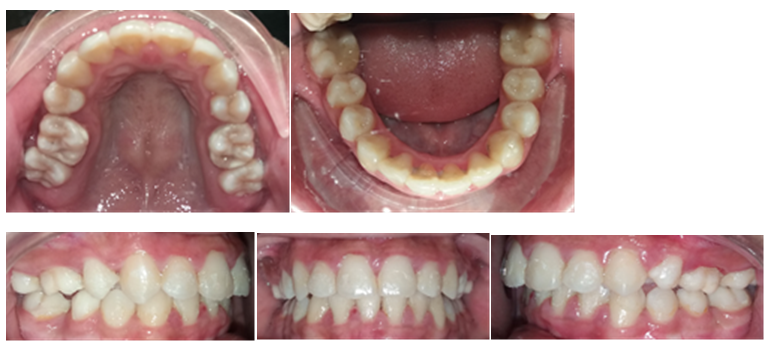

Figure 6. Foto intra oral sesudah perawatan

Setelah dilakukan ekstraksi premolar, perawatan dimulai dengan pemasangan braket roth menggunakan slot 0,022 dengan penjangkaran molar pertama dan molar kedua yaitu menginsersikan molar band pada gigi molar pertama dan buccal tube pada molar kedua Rahang Atas dan Rahang Bawah. Leveling dan alignment dilakukan menggunakan wire nikel-titanium mulai dari .012, .014, 0,016 hingga 0,017 × 0,025 pada Rahang Atas dan Rahang Bawah. Pada Rahang Bawah fase yang dilakukan adalah distalisasi 35, 45, dilanjutkan dengan 34 dan 44. Retraksi anterior dilakukan setelah retraksi kaninus terlebih dahulu menggunakan kawat stainless steel .017× .025 dengan stopper pada mesial 16, 26, 37 dan 47 dengan power chain. Setelah kaninus berhasil di retraksi maka dilakukan retraksi anterior menggunakan T-loop dengan wire stainless steel 0,016x0,022 pada Rahang Atas. Rahang Atas dilakukan intervensi step up dan step down pada Rahang Bawah. Mesialisasi 37, 47 dengan wire SS 0,017x0,025 dan power chain pada bagian bukal dan palatal pada 35, 45 yang telah diikat continues. Hasil akhir didapatkan overbite dan overjet yang normal dan relasi molar serta kaninus kelas I.(Gbr.5 dan 6). Clear retainer dipilih pasien pada akhir perawatan.

Dalam kasus ini, penggunaan double band menjadi pilihan yang tepat, dan pada akhir perawatan, tidak terdapat perubahan signifikan pada sudut MP-SN, yang menunjukkan bahwa mandibula tidak mengalami rotasi ke belakang. Setelah menyelesaikan perawatan ortodontik, relasi molar dan kaninus Kelas I berhasil dicapai di kedua sisi, di mana kondisi crowded dan deviasi garis median telah berhasil dikoreksi. Selain itu, inklinasi RA dan RB juga telah diperbaiki, sehingga sudut antar insisal yang baik dapat dicapai. Profil jaringan lunak pasien menunjukkan peningkatan yang signifikan, sesuai dengan tujuan perawatan yang telah ditetapkan.